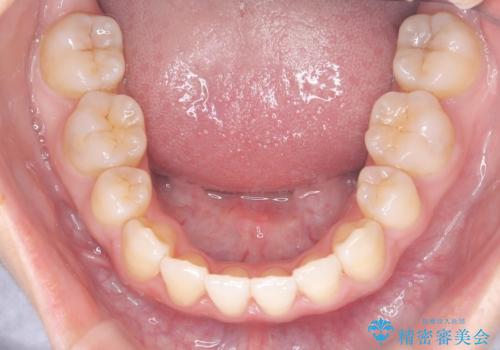

- 八重歯を主訴に来院されました。

左側犬歯が埋伏していましたが、第一小臼歯(4番目の歯)を抜歯したことでできたスペースに牽引し、右側の飛び出した八重歯を含め、歯全体を整列することができ患者様も満足していただきました。